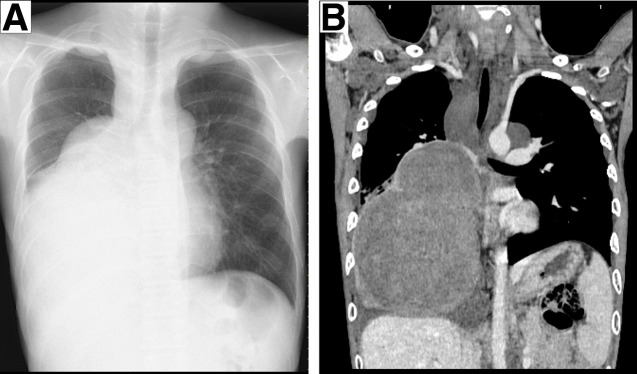

Case presentation: A 15-year-old boy presented with a large right mediastinal mass discovered on chest radiography at high school admission. Subsequent contrast-enhanced CT of the chest showed the development of a large tumor (16.0 × 12.5 × 11.8 cm) occupying approximately two-thirds of the right thoracic cavity, with atelectasis of the lower lobe of the right lung. The patient was histopathologically diagnosed with a benign schwannoma associated with neurofibromatosis type 1 through a thoracoscopic biopsy of the tumor and had received oral selumetinib at 50-70 mg/day for 11 months. Surgical excision was performed because of tumor progression and suspected malignant transformation. Right posterolateral thoracotomy with the opening of the 6th intercostal space was performed by extending the anterior skin incision along the abdominal rectus muscle and separating the 6th costal cartilage and diaphragmatic margin along the chest wall. The tumor was completely removed by resecting numerous adhesions between the tumor and the surrounding tissues and coagulating several nutrient vessels that flowed into the tumor, while resecting the lower lobe of the lung. The postoperative course was uneventful. The pathological examination revealed no malignancy. Subsequent contrast-enhanced CT of the chest revealed no residual tumors.